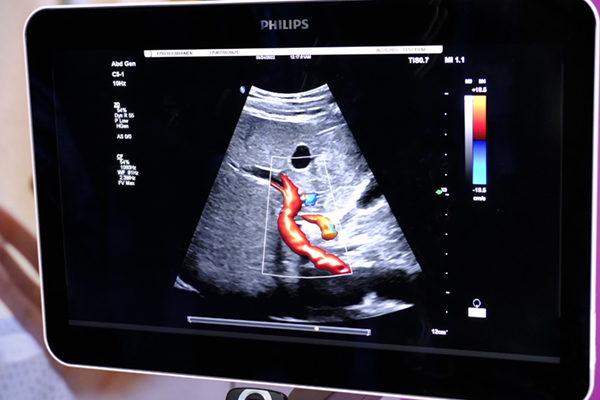

Philips(フィリップス)のUS領域では,据え置き型ハイエンド装置「EPIQ Elite」について,従来のversion 9に続くversion 10が発表された。version10は,血管の3Dイメージをより視覚的に描出し,新たに血管を細い分岐部まで明瞭に描出する「Flow Viewer」,造影剤注入時のコントラストを約200%強調する「Super-resolution microvascular imaging」などの新機能を搭載する予定で,まずは米国での展開が検討されている。

オリジナル画像(左)と「Super-resolution microvascular imaging」(右)。造影剤の移行を色で表現する(青→赤)